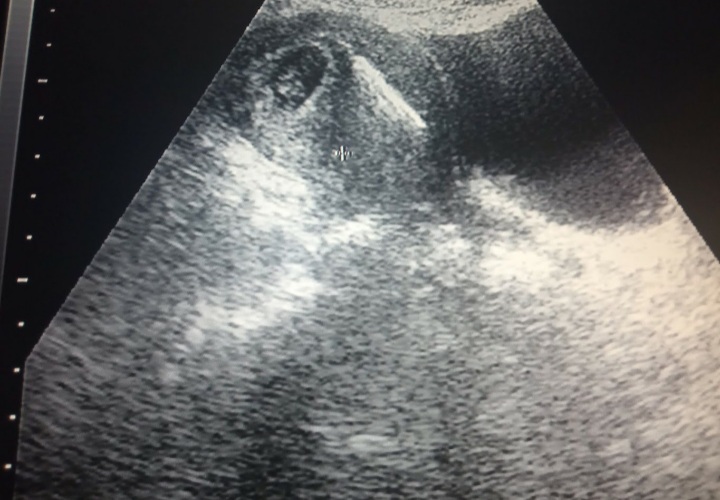

Debido a todo esto. Me coloco como metodo anticonceptivo una T de cobre. Ya que no debia salir embarazada. Por mi situación. Teniendo 2 años con la T. Comienzo a presentar malestar. Nauseas, dolor de cadera, cefalea. Y me bajo el periodo. el color del sangrado era diferente. En ese momento supe que estaba embarazada. Como trabajo en el area de salud. Le conte a unos amigos medicos pero medicos generales y nos ibamos a donde esta un ecógrafo para ver. pero no veíamos nada. Pero yo insistía estoy embarazada estoy embarazada.

Tanto fue mi insistencia que nos fuimos mi esposo y yo a la consulta con una ginecólogo. Ya cuando me toca pasar el no acepto pasar por que yo no tenía nada. Todo lo que tenía era un problema hormonal por lo de mi tiroide. Jeje pase a la consulta apenas la doctora me pone el traductor y vemos el monitor. Confirmadas mis dudas. hacen pasar a mi esposo y le dan la sorpresa.

Fue un momento de miedo, tristeza y alegría . Debido a que el embrión estaba al lado de la T de cobre si me extraían la T se traían al embrion. Pero no podían dejarla. podia ocasionar lesiones. Me dieron una semana de reposo. Y dar chance si eliminaba la T. En resumidas cuentas esto nunca sucedio. Todo mi embarazo fue dificil sangraba. Debia tener mucho reposo. Me atendia ginecologo, Internista, Endocrino. Me realizaban muchas pruebas. El internista me decia que no tomara el tratamiento para prevenir la pérdida.